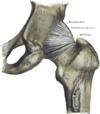

Ligaments

The hip joint is reinforced by four ligaments, of which three are extracapsular and one intracapsular.

The extracapsular ligaments are the iliofemoral, ischiofemoral, and pubofemoral ligaments attached to the bones of the pelvis (the ilium, ischium, and pubis respectively). All three strengthen the capsule and prevent an excessive range of movement in the joint. Of these, the Y-shaped and twisted iliofemoral ligament is the strongest ligament in the human body.[22] In the upright position, it prevents the trunk from falling backward without the need for muscular activity. In the sitting position, it becomes relaxed, thus permitting the pelvis to tilt backward into its sitting position. The iliofemoral ligament prevents excessive adduction and internal rotation of the hip. The ischiofemoral ligament prevents medial (internal) rotation while the pubofemoral ligament restricts abduction and internal rotation of the hip joint.[23] The zona orbicularis, which lies like a collar around the most narrow part of the femoral neck, is covered by the other ligaments which partly radiate into it. The zona orbicularis acts like a buttonhole on the femoral head and assists in maintaining the contact in the joint.[22] All three ligaments become taut when the joint is extended - this stabilises the joint, and reduces the energy demand of muscles when standing.[24]